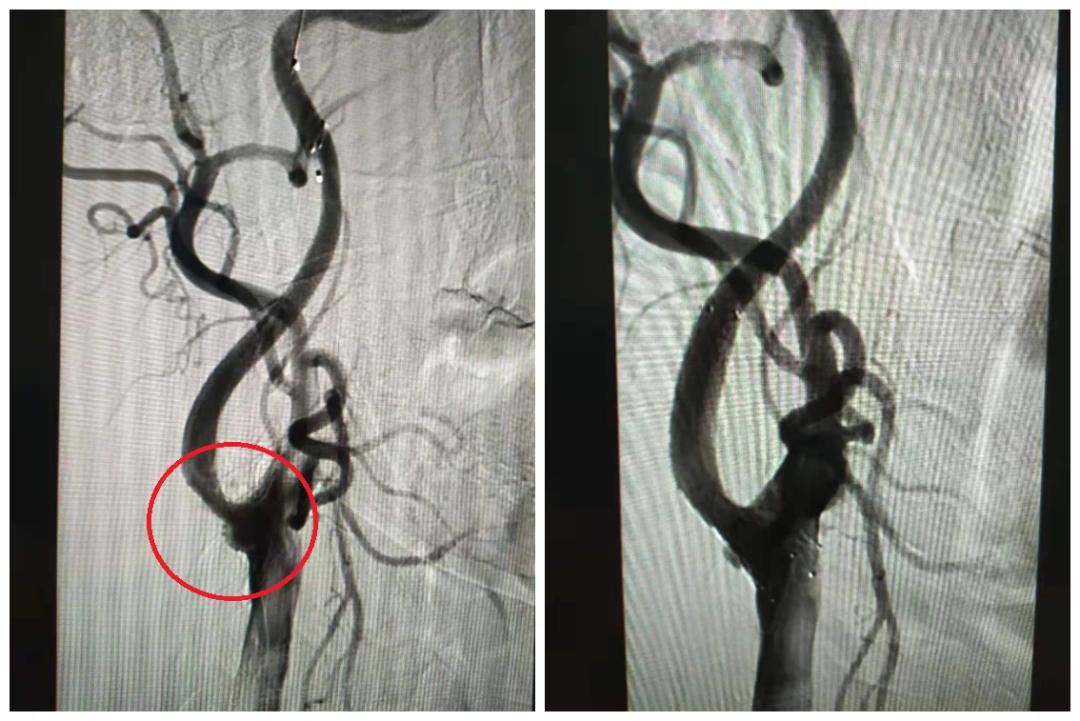

双侧椎动脉起始段闭塞(局部),右图含侧支代偿

双侧颈动脉C1段狭窄(局部)

右颈C1支架置入术前(左)术后(右)

左颈C1支架置入术前(左)术后(右)